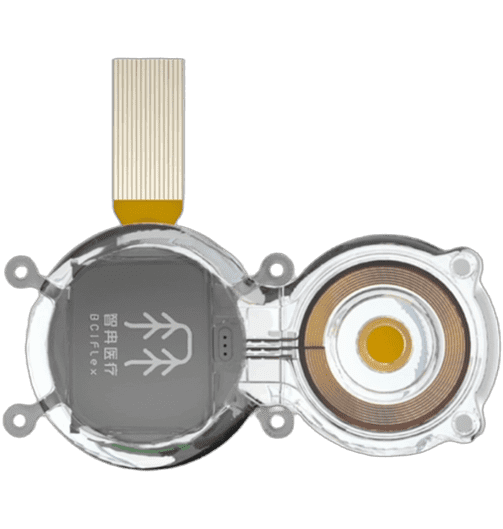

智冉医疗植入式信号采集器,契合患者真实的日常使用场景;采用全埋植设计,有效避免了开放创口带来的感染风险; 内置可充电电池,通过外部无线感应式充电器实现充电(该电池已顺利通过IEC62133 国际安全标准认证)。